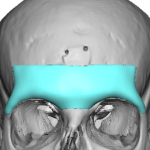

People considering custom jawline implants tend to ask a consistent set of questions. These generally fall into four categories: outcomes, safety, process, and recovery. What are custom jawline implants? Custom jawline implants are patient-specific implants designed from a 3D CT scan of your face. Unlike standard implants, they are digitally created to match your exact Read More…